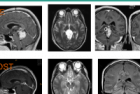

Índice de contenidos Glioma en región pineal Historia clínica: Glioma en región pineal Evolución: Conclusiones: Otros trabajos que pueden interesarle Glioma en región pineal Historia clínica: Glioma en región pineal Paciente mujer de 30 años que acude a urgencias por presentar cuadro de cefalea, vómitos y visión borrosa de dos semanas de evolución. No refiere … Sigue leyendo Glioma en región pineal